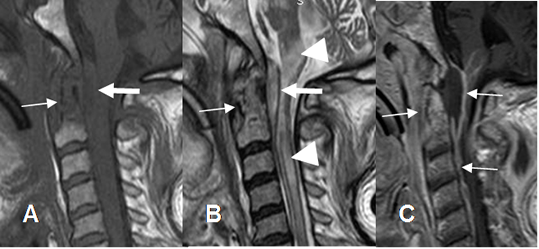

Fig 143 C. Absceso epidural.

A: RM sagital en T1 y B: RM sagital en T2. Igual paciente anterior. Alteración en la señal del arco anterior de C1 y la odontoides, por osteomielitis. (Flechas delgadas). Se encuentra colección epidural por detrás de la odontoides, que comprime la unión craneoespinal. (Flechas gruesas). Además hay hiperintensidad en T2 del bulbo y la medula, por isquemia. (Puntas de flecha).

C: RM sagital en T1 con contraste. Realce del contraste en el complejo C1-C2, los tejidos blandos prevertebrales, los bordes del empiema epidural y las meninges.